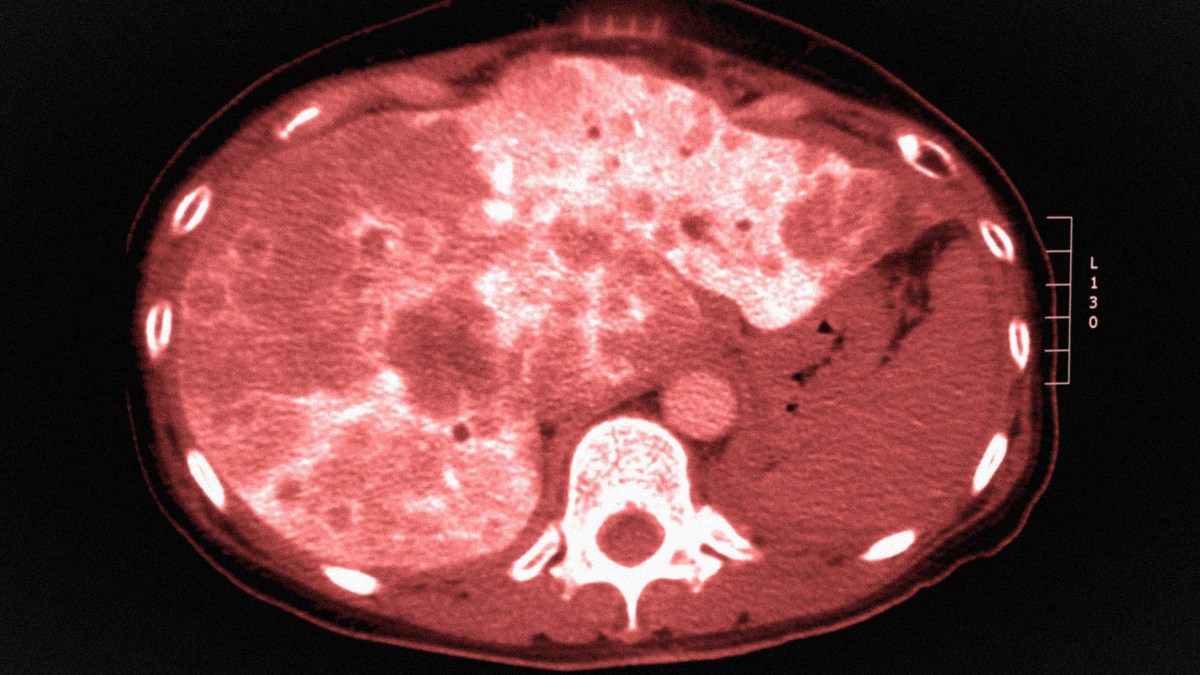

- A computed tomography colonography or “virtual colonoscopy” every five years